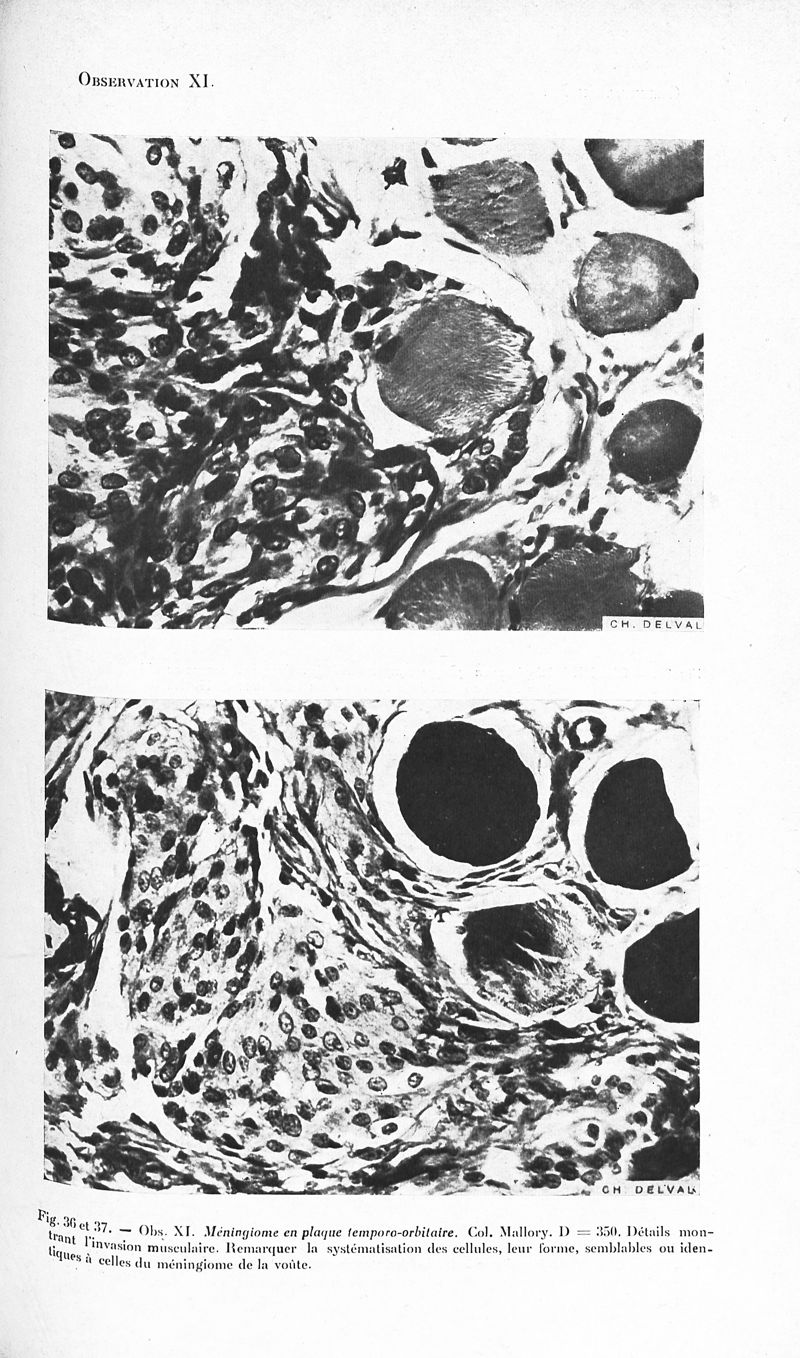

Revue neurologique

1928, vol 1. - Paris : Masson , 1928.